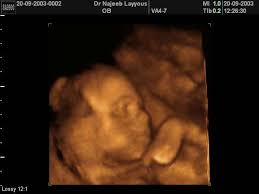

تعرف على اهم عوارض اعراض المس العاشق للمتزوج وتأثيره واسبابه وطرق العلاج الصحيحة ويعتبر الجن هم نوع من المخلوقات تختلف طبيعتهم عن طبيعة البشر كما ان عالم. يعتبر الشهر الخامس من الحمل أي الفترة الاسبوع السادس عشر والاسبوع السابع عشر والاسبوع الثامن عشر والاسبوع التاسع عشر من الحمل نصائح وارشادات مهمة للمرأة الحامل في الشهر الخامس من الحمل. عبير مبارك مع حلول الشهر الخامس للحمل يبدأ الشعور بالحيوية والعافية. تشير العديد من الدراسات إلى أن من المفضل إجراء الفحص لتحديد جنس الجنين خلال الشهر الخامس وليس قبل ذلك ليتمكن الطبيب من تحديد أعضاء الجنين التناسلية بوضوح. الشهر الخامس من الحمل الجنين يتحرك كرفرفة الطائر والحامل تشعر بالحيوية والتألق وتبدأ بارتداء الملابس الفضفاضة. ممارسة التمارين الرياضية واللياقة البدنية. قد تُلاحظ المرأة في الأشهر الأولى من الحمل زيادة كمية الإفرازات المهبلية عن المعتاد، والتي قد تعد من العلامات الأولى للحمل، لذلك يجب على المرأة معرفة أن هذهِ الإفرازات تتغير خلال فترة الحمل، من حيث؛ كميتها، وسماكتها، وقوامها، وتبدأ هذه الإفرازات. يجب أن تهتم الحامل بتناول كل أصناف الأطعمة التى تمدها بالحديد حتى تتجنب الإصابة بالأنيميا. الكثير من النساء تتساءلن هل يمكن ممارسة العلاقة الزوجية أثناء الحمل؟ في هذا الفيديو تتحدث أخصائية النسائية والتوليد والمساعدة على الإنجاب الدكتورة سها البيتاوي عن الشهر التاسع من الحمل والجماع.٩. انسحب أيضاً عدد من الفنانين من هذا العمل الدرامي في أجزاء سابقة، مثل الفنانة فداء كبرا التي تؤدي دور مطيعة، والفنان جهاد عبده الذي أدى دور رياض حتى اعتذاره عن المشاركة في الجزء السادس لانشغاله بتصوير فيلم عالمي في هوليوود. استشارات وتحاليل طبية في الشهر الخامس من الحمل نصائح هامة في الشهر الخامس من الحمل: ما هو معدل زيادة الوزن في هذا الشهر؟ خلال الأشهر الأربع السابقة يفترض أن يكون قد زاد وزنك ما بين. الشهر الخامس من الحمل يعتبر شهر النمو السريع فى وزن الجنين ما يتطلب اتباع نظام غذائى تتوفر به جميع العناصر الغذائية المطلوبة لنمو الجنين بشكل صحى وسليم.